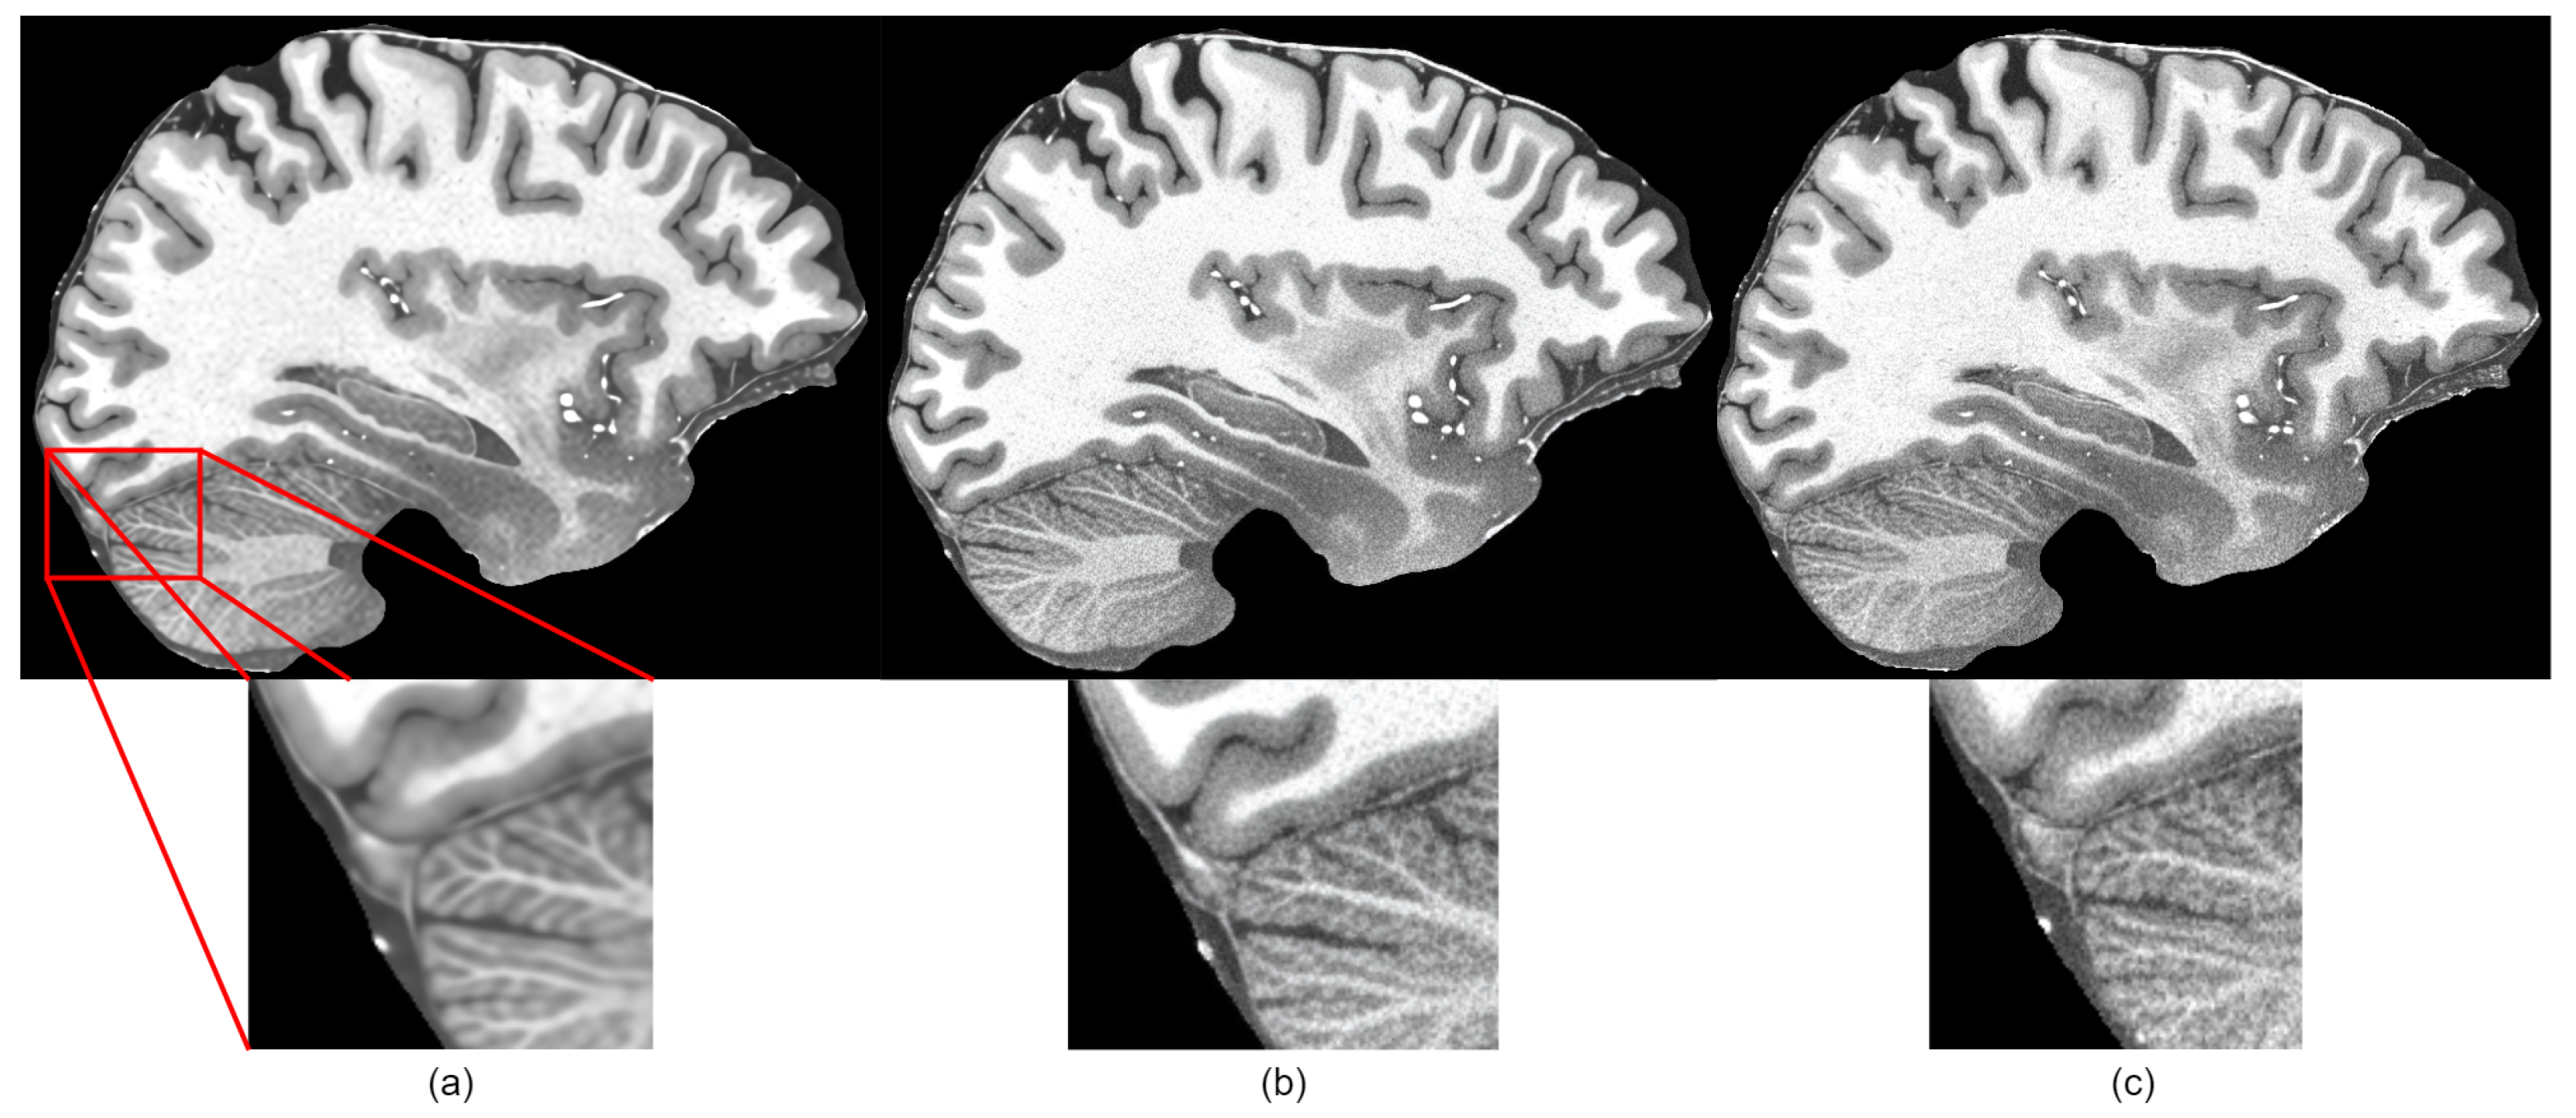

4. Results and Discussion

4.3. Results

4.4. Discussion